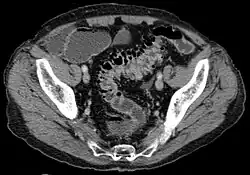

- Contrast CT is the investigation of choice in acute episodes of diverticulitis and where complications exist.

Complicated diverticulosis requires treatment of the complication. These complications are often grouped under a single diagnosis of diverticulitis and require skilled medical care of the infection, bleeding and perforation which may include intensive antibiotic treatment, intravenous fluids, and surgery. Complications are more common in patients who are taking NSAIDs or aspirin. As diverticulosis occurs in an older population such complications are serious events.